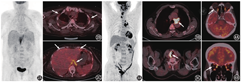

肌肉的生理性活动增加是最常见的引起骨骼肌代谢增高的原因。例如检查前健身会导致相应肌肉代谢增高,在FDG注射后的等待期间咀嚼口香糖会导致咀嚼肌代谢增高,呼吸困难的患者可出现呼吸肌(主要是膈肌和肋间肌)代谢增高(图2),慢性阻塞性肺疾病患者的呼气肌(主要是腹肌)会代谢增高,一些不自主的运动(如寒战、焦虑等造成的肌紧张)也可导致肌肉代谢增高[4]。患者在检查前进行适当的准备可避免肌肉代谢增高的情况。

肌肉生理性摄取的变化有时有一定的病理提示意义。在FDG注射后的等待期间说话可以导致双侧声带代谢对称性增高;单侧声带的代谢增高在除外声带病变后,需要考虑一侧喉返神经麻痹导致的对侧声带代偿性代谢增高,而喉返神经麻痹有时可因颈部或纵隔主肺动脉窗的肿瘤侵犯喉返神经引起(图3)。正常情况下,眼外肌的生理性活动活跃,FDG代谢比较高(尤其是内直肌),当一侧眼外肌代谢明显减低时,需要考虑眼外肌麻痹的可能,在阅片时注意颅底动眼神经、滑车神经、外展神经等走行区是否存在病变(图4)。另外,由于失神经支配可能导致骨骼肌的葡萄糖代谢增加,周围神经病变可能会导致所支配的肌肉代谢增高,如颈部手术若损伤了副神经,可能导致同侧的斜方肌代谢增高[5]。